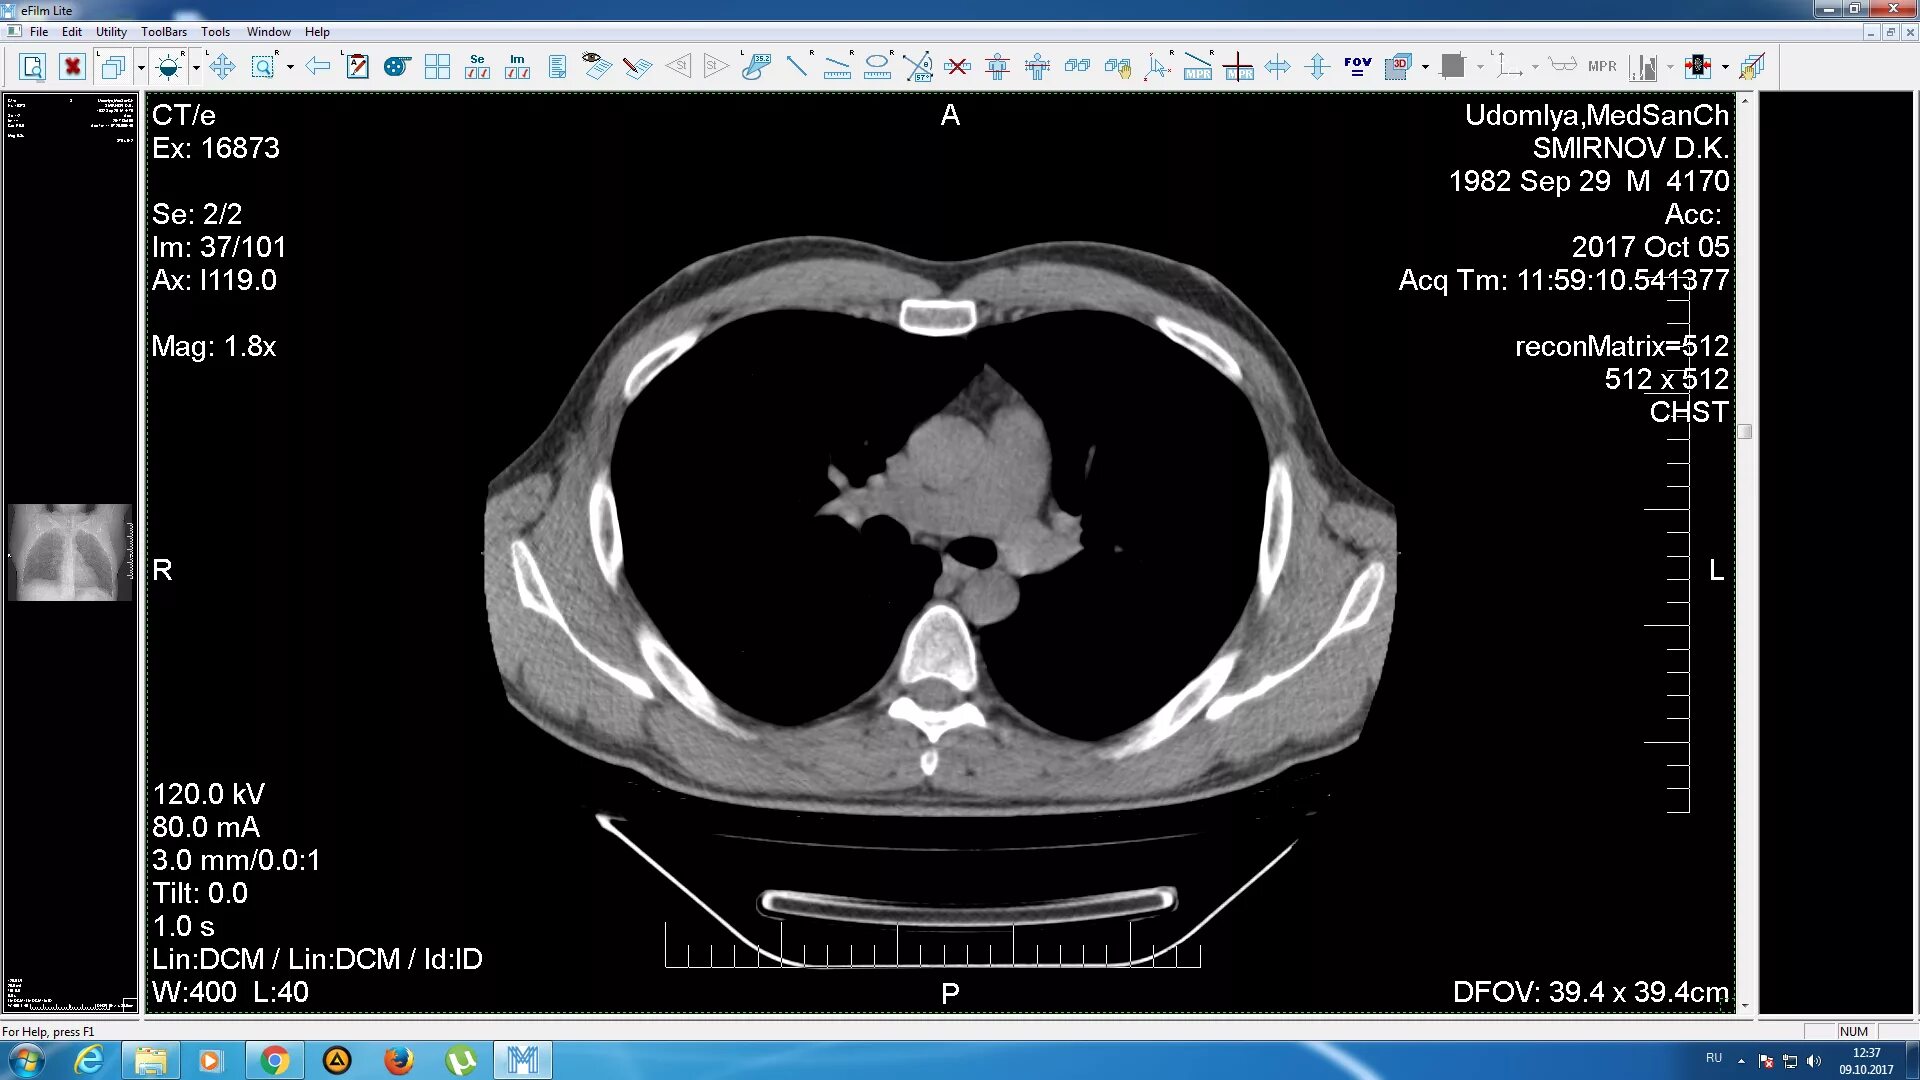

Данные кт